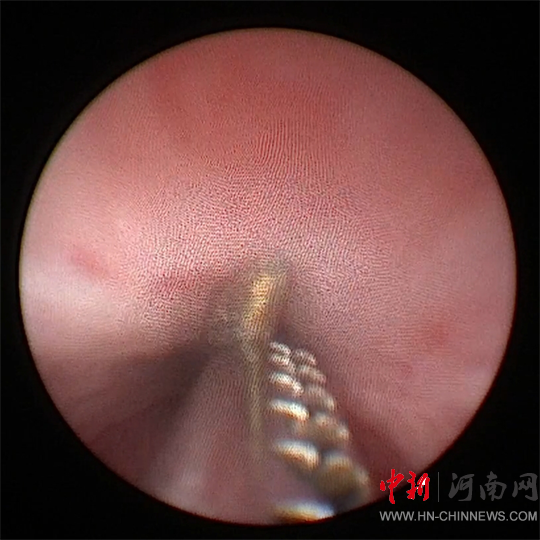

徐海亮團隊經(jīng)過

充分術(shù)前準備

采用小兒輸尿管鏡

和異物鉗進行手術(shù)

因鋼針嵌頓于尿道壁

并伴局部組織炎癥水腫

徐海亮在精細操作下

謹慎調(diào)整異物角度

一點一點往外取

歷時20分鐘

順利將鋼針取出